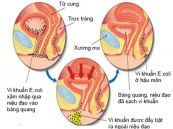

Đường tiết niệu (đường tiểu) là một trong những bộ phận dễ bị nhiễm trùng nhất trong cơ thể. Tất cả mọi người đều có nguy cơ mắc bệnh. Tuy nhiên, tỷ lệ nhiễm trùng đường tiết niệu ở nữ có thể lên đến 50% hoặc hơn. Đặc biệt, những người đã lập gia đình có khả năng cao bị nhiễm trùng đường tiểu ít nhất một lần trong đời. Tham khảo bài viết dưới đây để hiểu rõ hơn về bệnh lý này nhé!